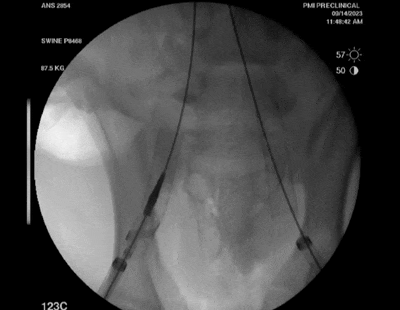

Recana栓塞收集器放置

利用標(biāo)準(zhǔn)的熒光透視/IVUS引導(dǎo)技術(shù),Recana可以很容易地被已經(jīng)進(jìn)行深靜脈血栓和深靜脈支架栓塞切除。